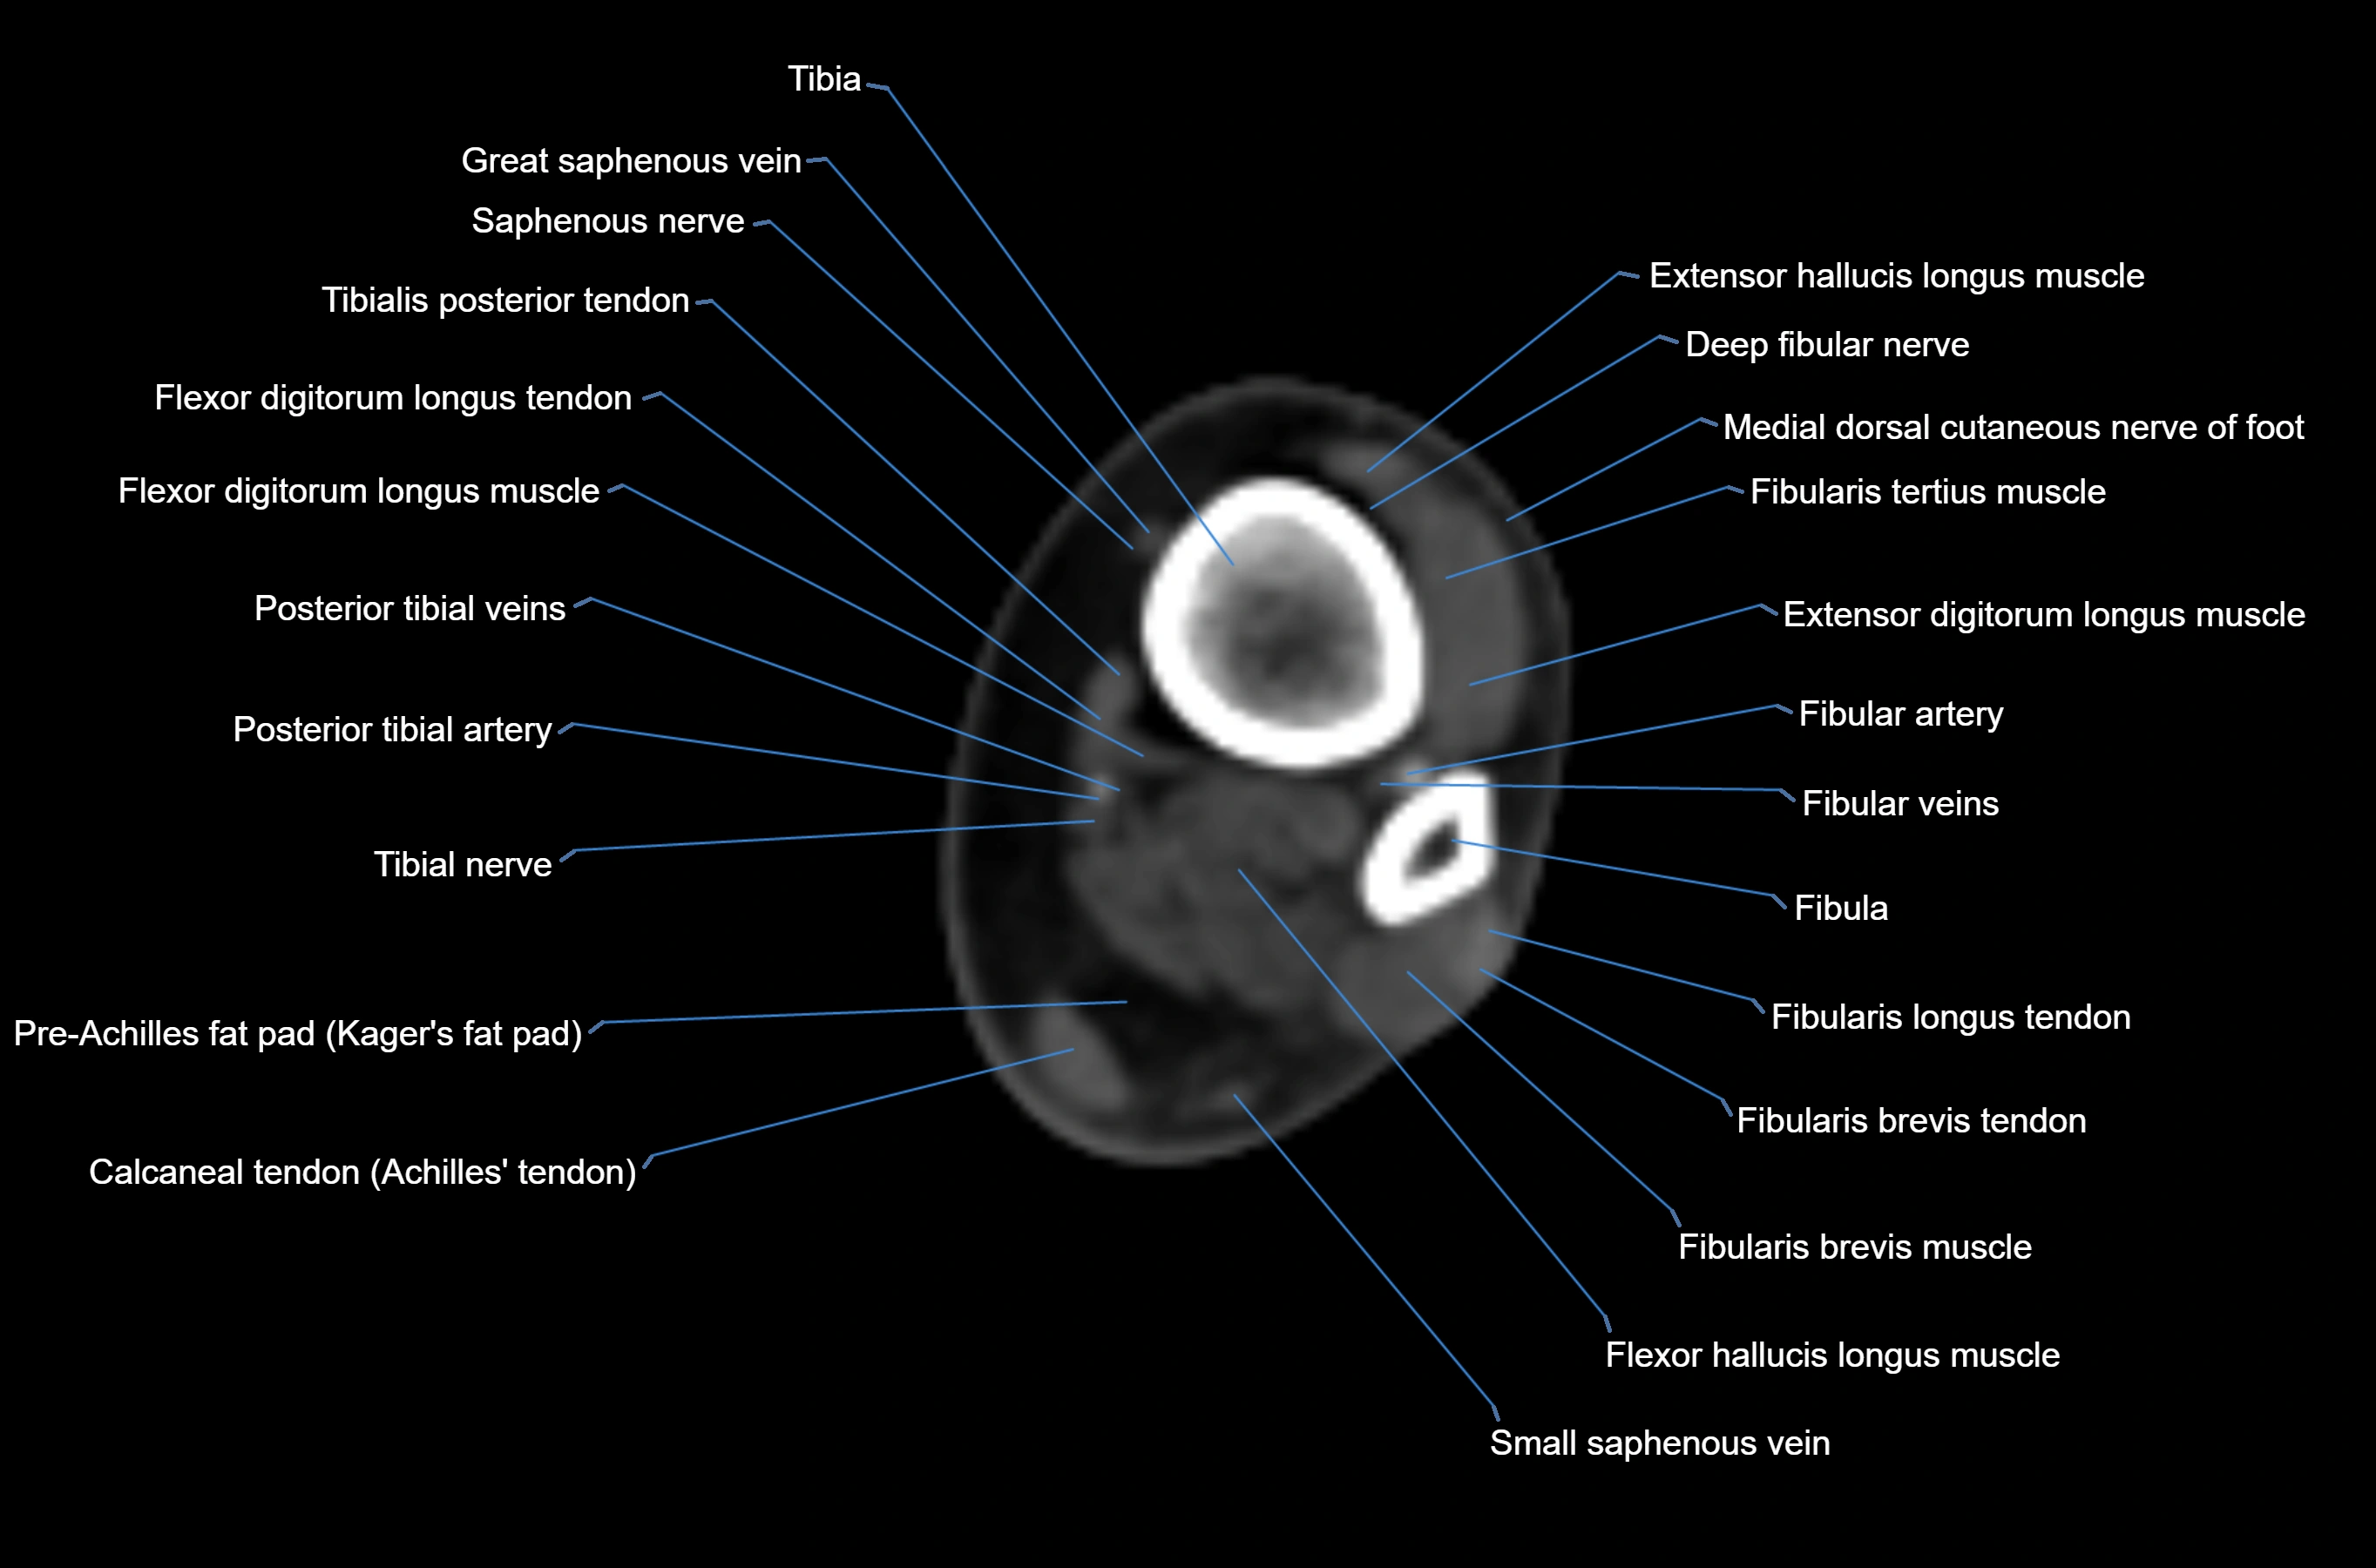

CT image